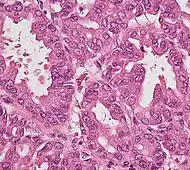

Histopathology

The most common form of pancreatic cancer (adenocarcinoma) is typically characterized by moderately to poorly differentiated glandular structures on microscopic examination. There is typically considerable desmoplasia or formation of a dense fibrous stroma or structural tissue consisting of a range of cell types (including myofibroblasts, macrophages, lymphocytes and mast cells) and deposited material (such as type I collagen and hyaluronic acid). This creates a tumor microenvironment that is short of blood vessels (hypovascular) and so of oxygen (tumor hypoxia).[2] It is thought that this prevents many chemotherapy drugs from reaching the tumor, as one factor making the cancer especially hard to treat.[2][3]

| Cancer type | Relative incidence[11] | Microscopy findings[11] | Micrograph | Immunohistochemistry markers[11] | Genetic alterations[11] |

| Pancreatic ductal adenocarcinoma (PDAC) | 90% | Glands and desmoplasia | ![]() | ||